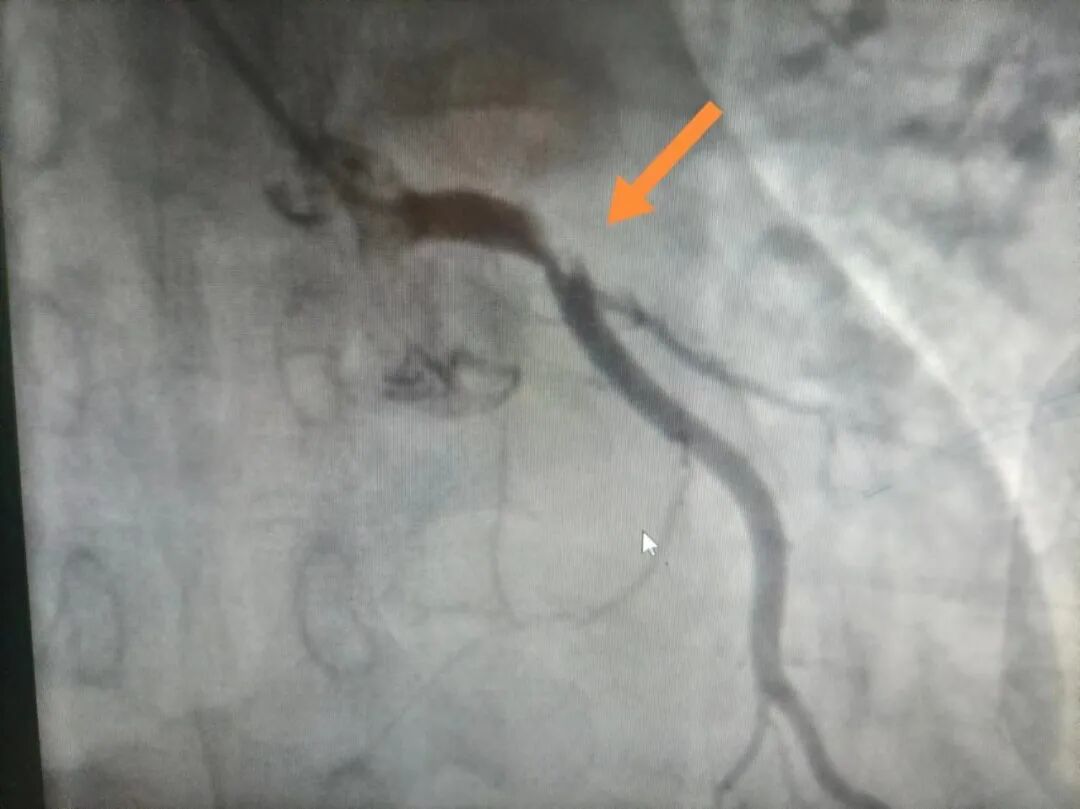

一个病例分享:一位37岁男性病人胸痛胸闷1小时50分入院,自诉无明显诱因出现胸痛胸闷症状,位于心前区、胸骨中段,持续性疼痛,伴大汗、恶心,测血压82/50mmHg,急查心电图示异位心律,广泛前壁心肌梗死,患者病情危重,立即推入导管室行冠脉造影术,冠脉造影显示左主干末端负荷血栓,前降支开口100%闭塞,回旋支开口90%狭窄,可见血栓影,给予血栓抽吸,抽吸出大量红色血栓,后于前降支开口植入支架一枚,七天后患者好转出院,这样的例子数不胜数,无数次的在时间与生命赛道上与死神抢病人。

造影后